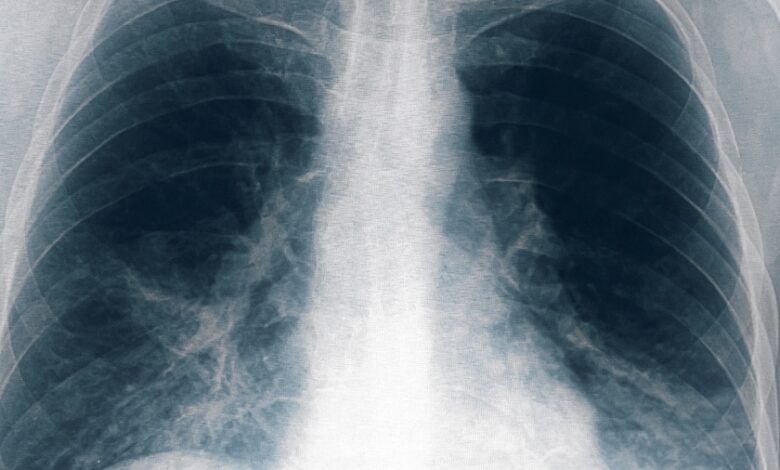

Neumonía bilateral por legionella: ocho nuevos casos en Tucumán

Otras ocho personas resultaron afectadas por el brote de neumonía bilateral causado por la bacteria legionella, una de ellas en estado grave, tras un cambio en el criterio de selección de los pacientes, con lo que suman 13 casos en total y seis fallecidos, informó el ministro de Salud de Tucumán, Luis Medina Ruiz.